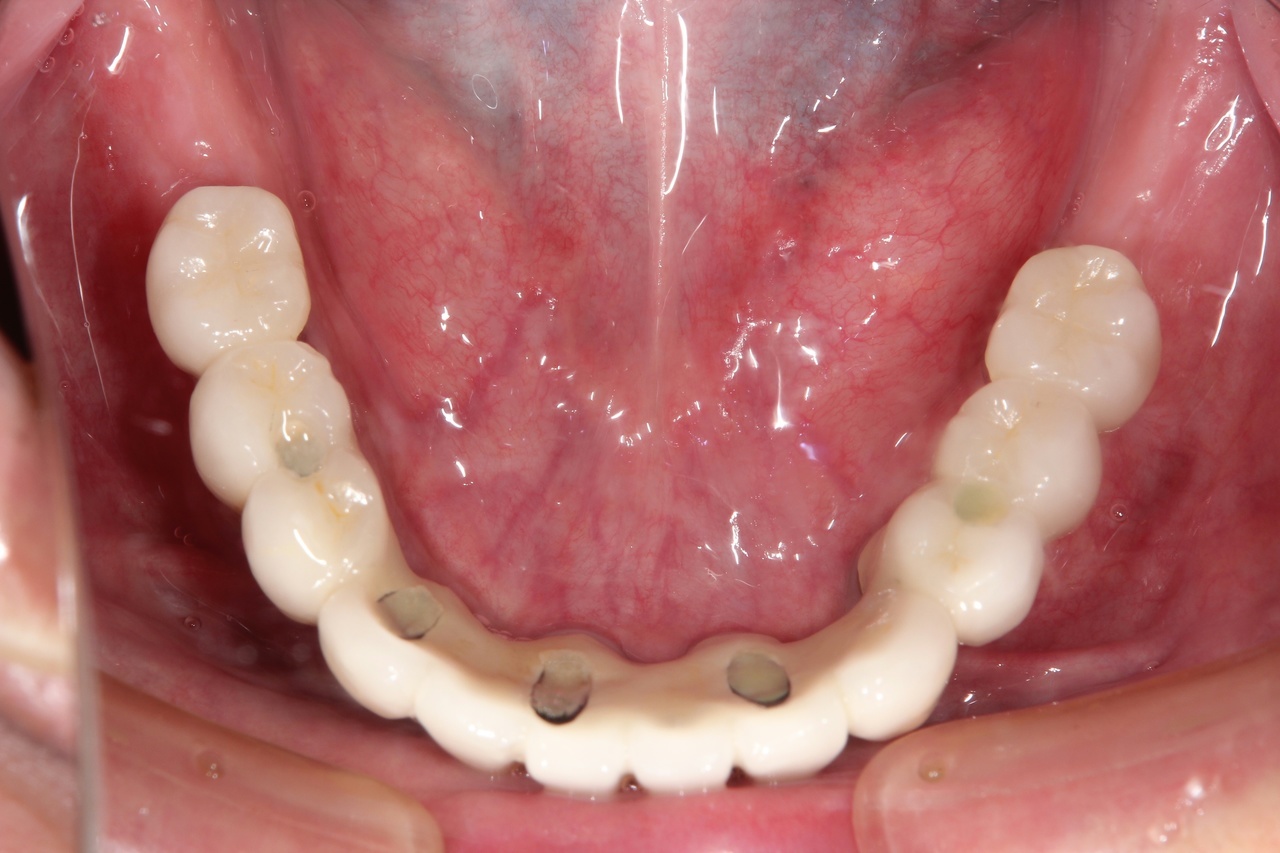

最終的な被せ物装着

インプラントがしっかり骨に定着したら、型取りをして、最終的な被せ物を製作し、装着します。

6本のインプラントで、12本の歯を並べる(下顎・仮歯代含む)

(裾野市在住 女性)

お口の中の状態

被せ物を外した状態

6本のインプラントを埋入し、12本の歯を並べています。第二大臼歯を作らない場合の理想的な治療法になります。

【下顎インプラント6本で12本の歯を回復するスクリュー固定タイプ】

インプラント手術:250,000円×6本=1,500,000円

静脈内鎮静法:0円

既製アバットメント:90,000円×6個=540,000円

メタルボンド:130,000円×12本=1,560,000円

マルチアバットメント:25,000円×6個=150,000円

連結料:10,000円×11カ所=110,000円

仮歯:50,000円×6本=300,000円

ポンティック:10,000円×6本=60,000円

ラジオグラフィックガイド(14本):23,000円

埋入ガイド(6本):73,000円

総額:4,316,000円+税